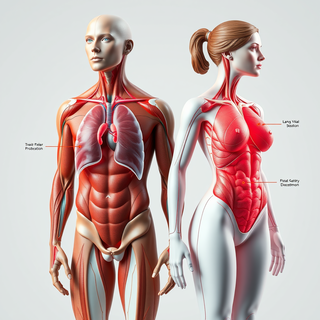

Generate ultra-realistic microscopic imagery for medical research.Open

Generate ultra-realistic microscopic imagery for medical research.Open